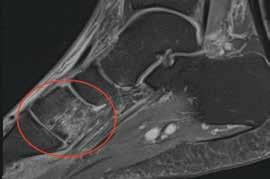

Dr.med. Andreas Krüger is a Swiss board orthopaedic and trauma surgeon in Zurich, who specialises in knee and shoulder surgery. Andi is a second generation of tournament doctors for equine sports, known as Polodoc since 2013

Painful Foot Injury

Laser – The new kid on the block

The foot of the polo player in polo is very important as an anchor and link to the saddle and consequently to the horse. With the high levels of loading while riding, massive amounts of force runs through the foot and already small injuries can be very painful. Most foot injuries are a result of twisting or slipping. Due to the limited space in polo boots the use of auxiliary stabilisers is problematic. Initial correct diagnostics and treatment is crucial for a fast and safe return to sport.

Foot Anatomy

Most structures in the foot are fairly superficial and the cushioning through subcutaneous tissue as muscle and fat is minimal. The foot is divided in hindfoot, midfoot and the forefoot. The midfoot is the most used in polo due its contact with the stirrup. The foot is principally comprised of 28 bones. Where two bones meet a joint is formed – often supported by strong ligaments.

Most important bones in the midfoot

The midfoot (navicular, cuneiforms, and cuboid tarsal bones) meets the metatarsals at the tarsometatarsal joint, also known as the Lisfranc joint complex.

Cuboid

The cuboid bone is a square-shaped bone on the lateral aspect of the foot. The main joint formed with the cuboid is the calcaneocuboid joint, where the distal aspect of the calcaneus articulates with the cuboid.

Cuneiform bones

Here are three cuneiform bones in the foot: the medial, medial (intermediate), and lateral cuneiforms. These bones, along with the strong plantar and dorsal ligaments that connect to them, provide a good deal of stability for the foot.

Mechanism of Injury

Most injuries are as a result of twisting and turning. Even hyperextension or hyperflexion may have an impact to the joint line. During these impacts, the stabilisers as the ligaments and the joint capsule are stressed. With ongoing load, either these structures brake or the bone itself fails. Even low impact may result in swelling and painful restriction in full weight bearing.

Diagnostics

Initial clinical examination is essential. When swelling, hematoma or instability / deformity is present in combination with limited weight bearing, further examinations are indicated. Conventional (standing) X-rays are a good baseline diagnostic tool to detect dislocation and displaced fractures. Further details can be pictured with CT (Computer Tomography) where the bones and joints can be assessed by slices from different layers and angles.

Treatment

Timing is crucial. Fast initial diagnostics and treatment creates a quicker recovery. When the injury happens hematoma and soft tissue swelling always occurs. Direct compression and cold therapy are beneficial in minimising the disabling swelling. Local myofascial taping can help to reduce swelling and increase lymph drainage. Adequate adaptions on the boots may be needed.

Knowledge www.polotimes.co.uk 46 Polo Times, March 2023 Medical Insight: Polodoc

The regions of the foot Photography courtesy of Polodoc Cuneiform bones

Braces like carbon insoles can minimize the joint movement and equalize the load to all other areas so that the injured region is less charged. When a decision towards the treatment regime is taken also new techniques such as laser treatment could help to minimise pain and improve the healing process.

For more information on Polodoc contact Andreas Krüger at drmedkrueger@gmail.com or www.polodoc.ch

Knowledge www.polotimes.co.uk 47 Polo Times, March 2023 Medical Insight: Polodoc

Laser treatment can help to minimise pain and improve the healing process Fast initial diagnostics and treatment creates a quicker recovery Carbon insoles act as a brace and can minimise the joint movement Carbon insole inside a polo boot